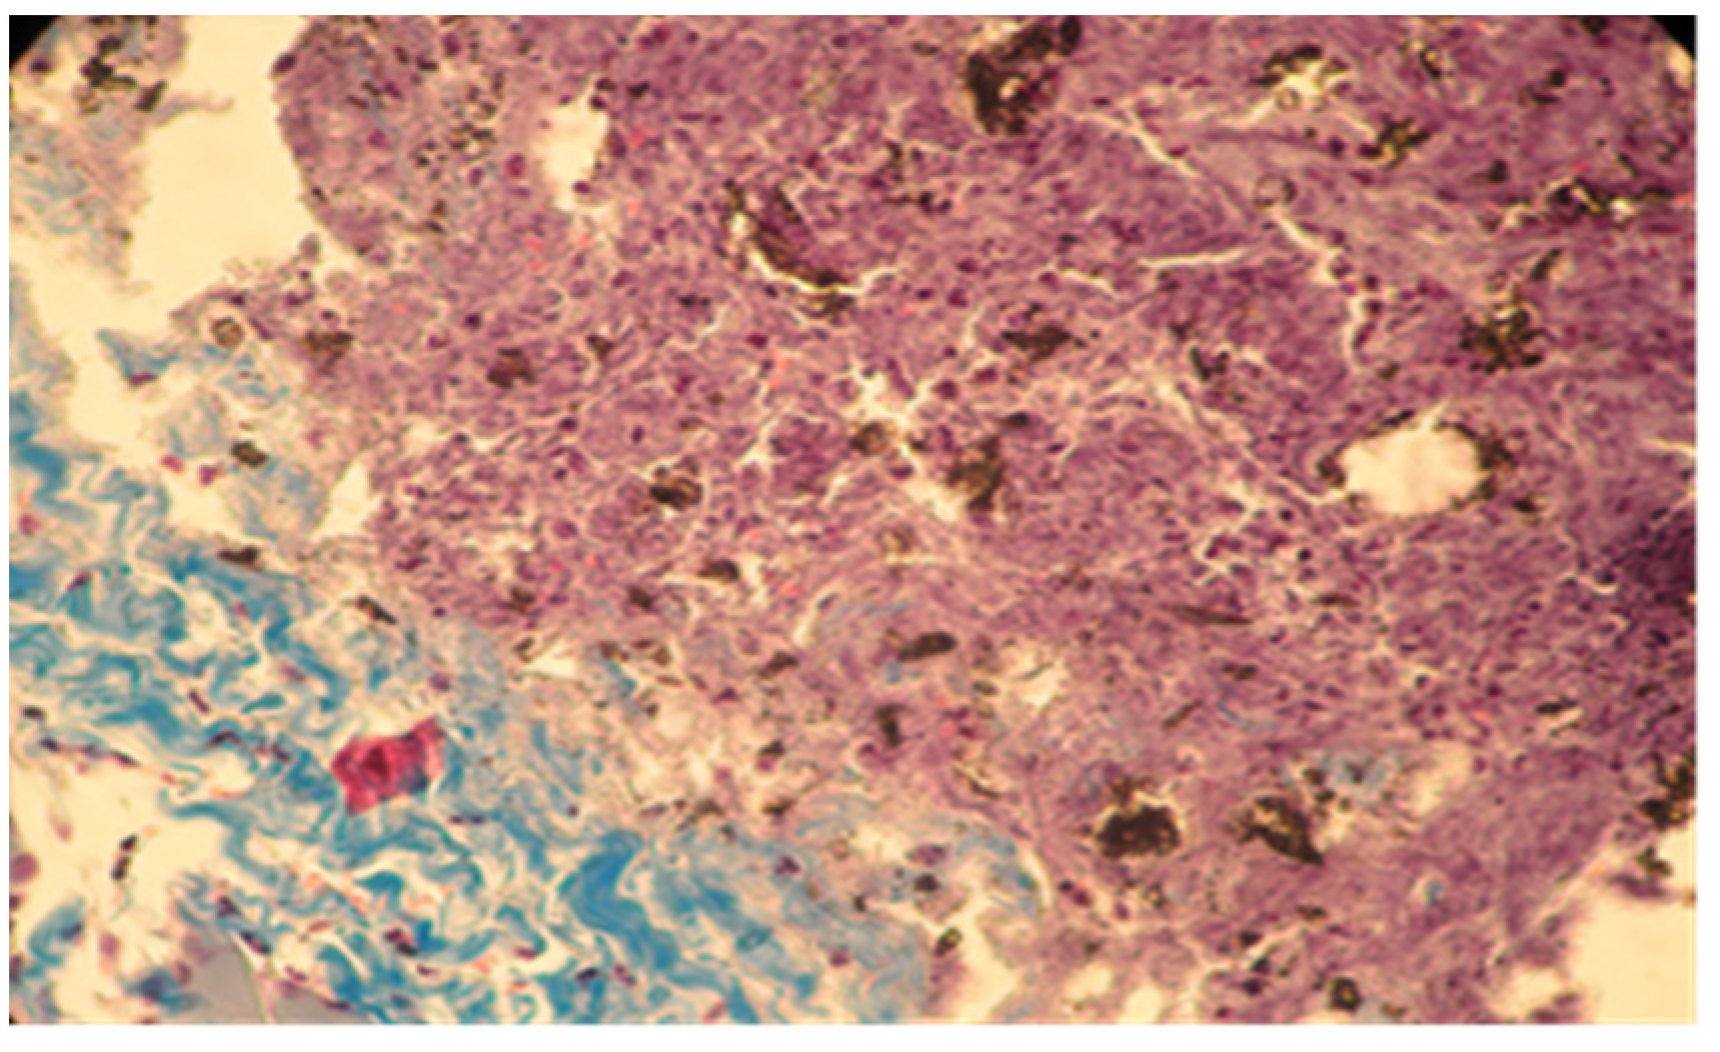

In group A (implanted with MTA) we noticed a well-defined area of peripheral necrosis (surrounding the biomaterial) in which incompletely resorbed MTA fragments and an intense influx of leukocytes consisting of macrophages, histiocytic cells, and neutrophils were present, together with a high number of fibroblasts and collagen fibers (Figure 4 and Figure 5).

Figure 4. Group A. Subcutaneous conjunctive tissue. Area of necrosis, intense leukocyte infiltration.

Applsci 11 06519 g004

Figure 5. Group A. Buffer zone, consisting of fibroblast proliferation and collagen fiber synthesis. Col. Trichrome Masson, ×200.